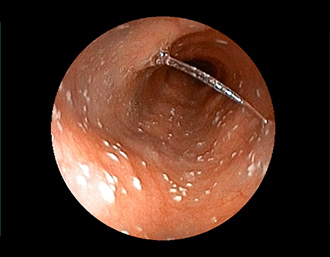

症例3:十二指腸潰瘍(53才男性)

1年前からの慢性胃痛を主訴に当院受診。十二指腸球部前壁に深くて大きな潰瘍(Stage A1)があり、潰瘍底は厚い白苔に覆われ、一部白苔のはみ出しを認める。潰瘍周囲粘膜は浮腫を伴っている。ボノプラザンフマル酸塩投薬で治療開始しました。